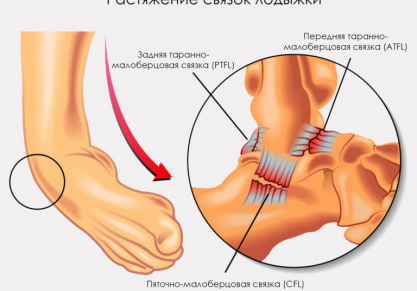

Срок восстановления разрыва и растяжения связок голеностопного сустава

Сколько заживает разрыв связок голеностопного сустава. Как ускорить восстановление. Медикаментозные способы лечения травмы.